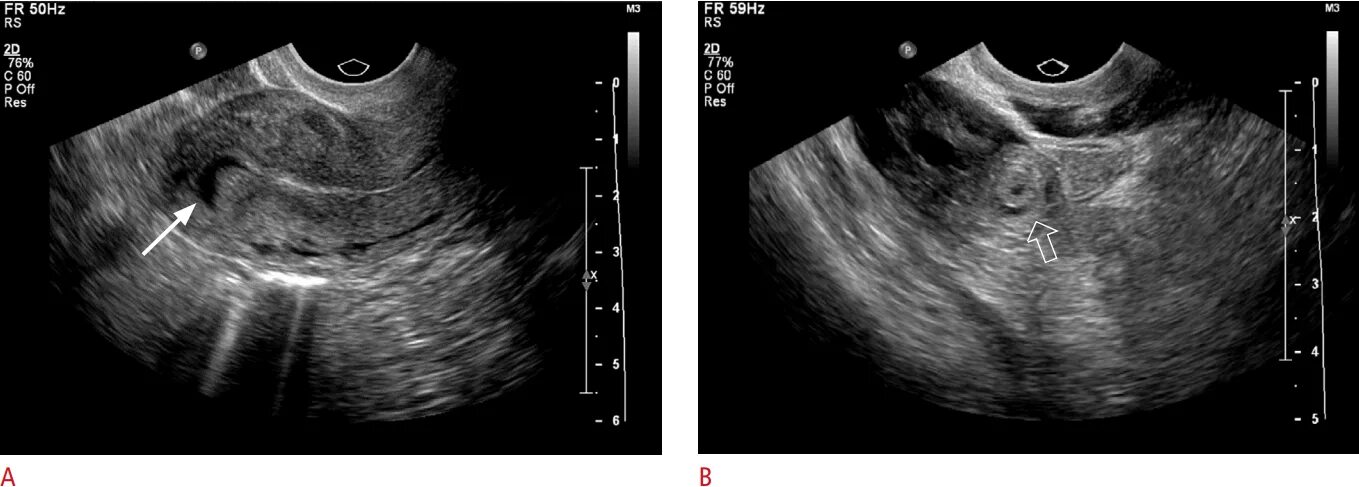

Можно ли на узи увидеть внематочную беременность